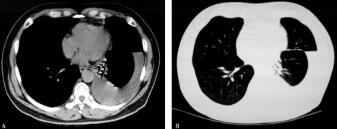

1.胸部CT(2011年12月19日引流900ml胸腔积液后):左侧胸腔积液伴左肺下叶膨胀不全,左侧叶间积液,纵隔及左肺门增大淋巴结,心包少量积液(图1A纵隔窗、B肺窗)。

图1